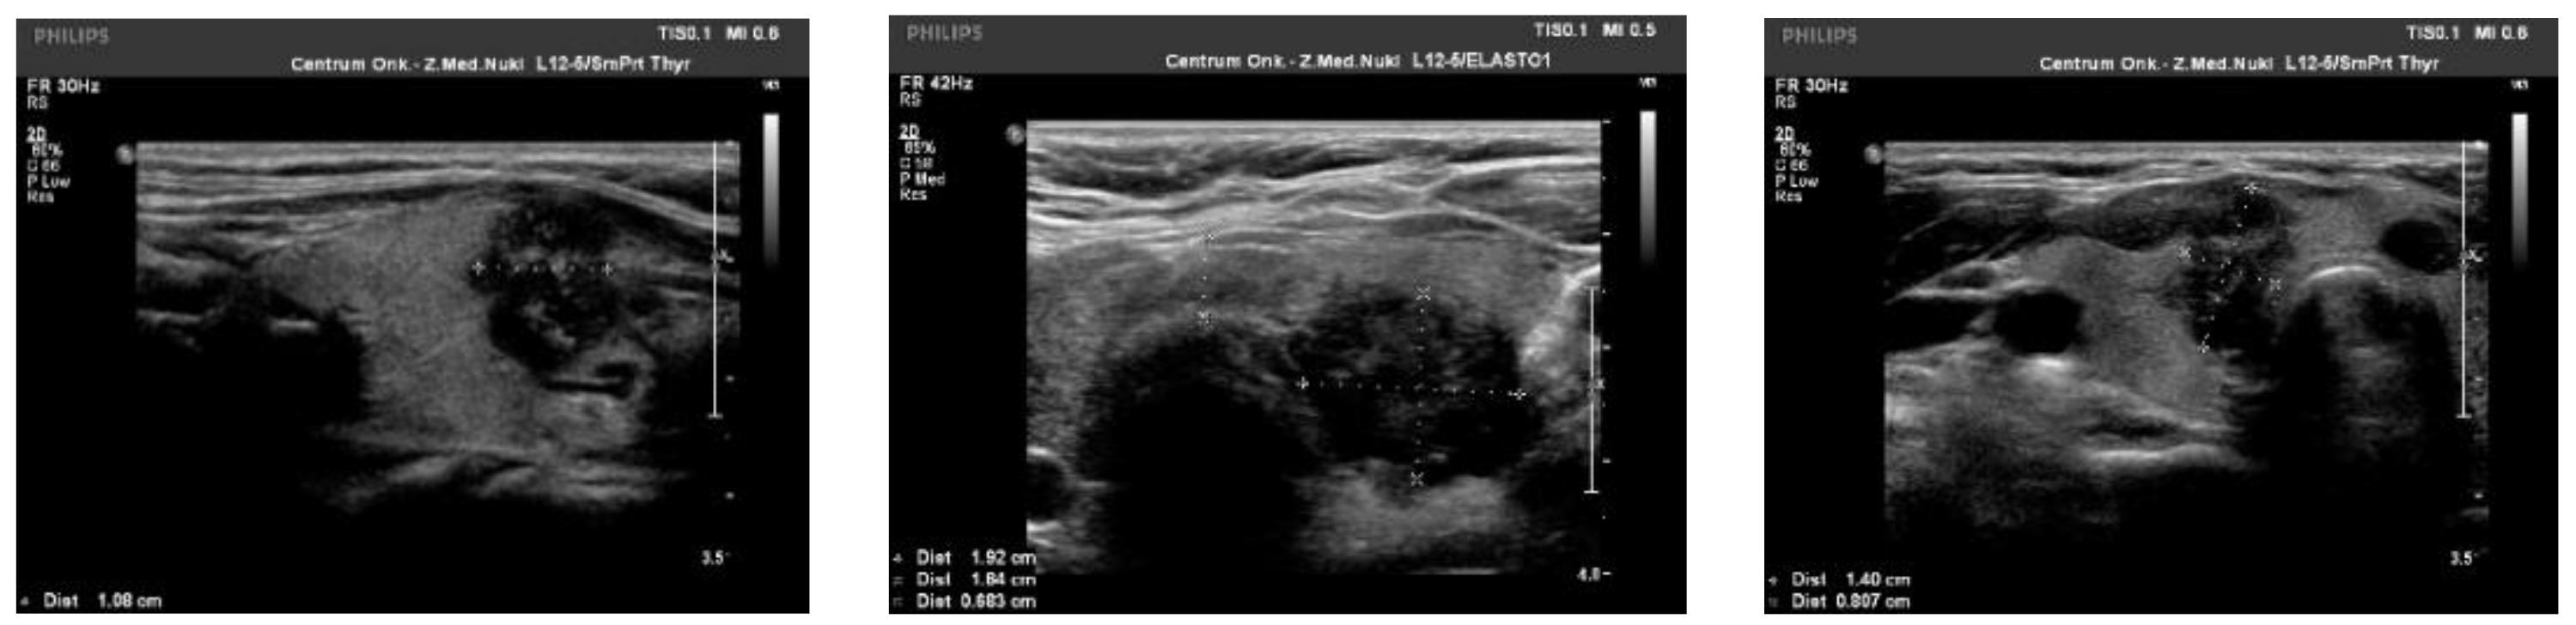

We observed the strongest correlation between hypoechogenicity (p-value < 0.05) and BRAF V600E positivity, although four more malignancy-associated features (taller-than-wide shape, blurred margins, microcalcifications, and absence of “halo”) were also more frequent in the BRAF V600E (+) group. PTC risk increased with a higher EU-TIRADS score (p-value = 0.04). US images of BRAF V600E (+) and BRAF V600E (−) PTCs are presented in Figure 2 and Figure 3, respectively.

Figure 2.

US image of BRAF V600E positive PTCs: solid structure (2 points), deeply hypoechogenic, (3 points), taller-than-wide orientation (3 points), blurred margins (2 points), microcalcifications (3 points)—13 points = TIRADS 5.

Figure 3.

US image of BRAF V600E negative PTCs: solid structure (2 points), isoechogenic or slightly hypoechoic (1–2 point), taller-than-wide orientation (3 points), blurred margins (2 points), absence of calcifications (0 points)—8–9 points = TIRADS 5.